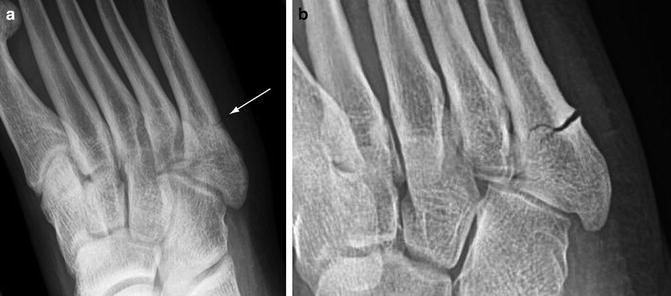

Chụp X-quang

Một vết nứt nhỏ ở xương đôi khi khó nhận ra trên phim X-quang nên phương pháp này có thể không giúp chẩn đoán gãy xương do mỏi trừ khi xương đã bắt đầu lành. Khi này, xương tạo ra một vết chai có thể nhìn thấy nhờ vào tia X.